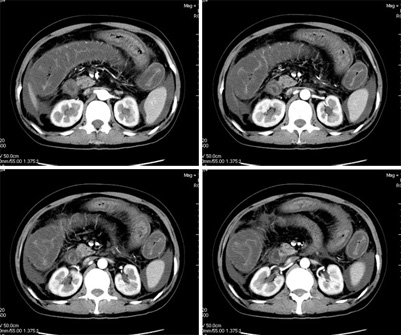

女,42岁,既往体健,近一月来无明显诱因下出现恶心呕吐,同时出现腹泻,否认有结核病,糖尿病史,入院后检查,胸片未见明显异常,ppd阴性,肝转氨酶正常,腹水检查,在漏出液与渗出液之间,胃镜慢性浅表性胃炎,盆腔b超.盆腔积液.

平扫一部分图片

真是少见!至少本人从未见过!整个消化道除了胃壁以外整套小肠及结肠肠壁均不同程度增厚水肿,肠壁间未见积气,亦未见明显的血运障碍(肠细膜上动静脉均显示很好)。盆腹腔积液。

真是少见!至少本人从未见过!整个消化道除了胃壁以外整套小肠及结肠肠壁均不同程度增厚水肿,增强明显分层[粘膜层及浆膜层明显强化,粘膜下层强化轻]。结合病史考虑肠道缺血改变[病因待查--血管炎,结缔组织疾病等]

真是少见!至少本人从未见过!整个消化道除了胃壁以外整套小肠及结肠肠壁均不同程度环形增厚,肠壁密度均匀呈“晕圈”样改变,粘膜下层低密度,粘膜层和外层为相对高密度。增强强化不明显。结合病史考虑肠道急性缺血改变。腹水。形成原因肠系膜动脉栓塞、还是静脉血栓形成看不懂。

真是少见!我也从未见过!整个消化道除了胃壁以外整套小肠及结肠肠壁均不同程度同心圆样增厚,肠壁密度均匀呈“晕圈”样改变,粘膜下层低密度,粘膜层和外层为相对高密度;增强强化不明显。腹腔各个间隙内液性密度积液影,结合病史考虑:肠道慢性中毒性改变(药物性中毒可能性大)。腹水形成原因?